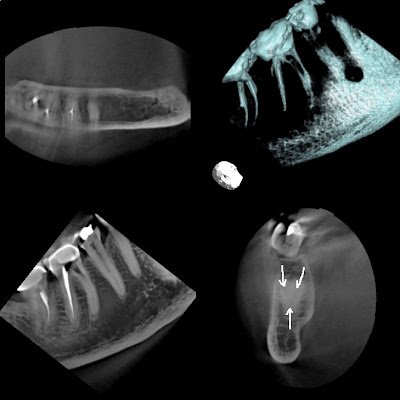

I completed this RCT in Nov 2011. Palatal lesion seemed to improve, but patient symptoms returned. In this particular case, I found only 2 canals. After extensive searching under the microscope, I determined that this must be one of those tricky 2 rooted Mx molars. Since symptoms returned, we took CBCT to see if I missed anything.

CBCT reveals that I did miss a DB canal. However, looking closely at the axial view, my assumption that this is a 2 rooted molar was correct. The palatal and DB roots were fused as one. Sagittal view shows the missed DB canal. Axial view shows the missed DB as well. The CBCT is now a map for retreatment.

As explained, the axial and sagittal view provided by CBCT is invaluable. More information provides for better treatment. This post should demonstrate the level of complexity of molar endodontic therapy even with the use of the operating microscope and the benefit of 3D imaging over 2D imaging alone.